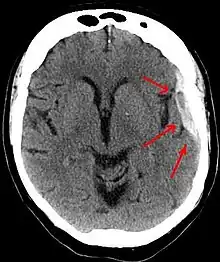

Subdural hematomas occur most often around the tops and sides of the frontal and parietal lobes.[3][2] They also occur in the posterior cranial fossa, and near the falx cerebri and tentorium cerebelli.[3] Unlike epidural hematomas, which cannot expand past the sutures of the skull, subdural hematomas can expand along the inside of the skull, creating a concave shape that follows the curve of the brain, stopping only at dural reflections like the tentorium cerebelli and falx cerebri.

On a CT scan, subdural hematomas are classically crescent-shaped, with a concave surface away from the skull. However, they can have a convex appearance, especially in the early stages of bleeding. This may cause difficulty in distinguishing between subdural and epidural hemorrhages. A more reliable indicator of subdural hemorrhage is its involvement of a larger portion of the cerebral hemisphere. Subdural blood can also be seen as a layering density along the tentorium cerebelli. This can be a chronic, stable process, since the feeding system is low-pressure. In such cases, subtle signs of bleeding—such as effacement of sulci or medial displacement of the junction between gray matter and white matter—may be apparent.

Fresh subdural bleeding is hyperdense, but becomes more hypodense over time due to dissolution of cellular elements. After 3–14 days, the bleeding becomes isodense with brain tissue and may therefore be missed.[20] Subsequently, it will become more hypodense than brain tissue.[21]